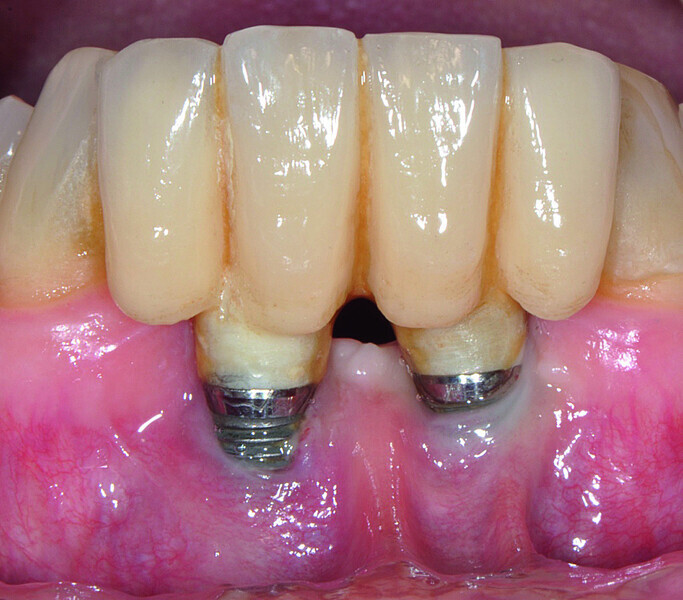

Fig. 1a: Implant in position #14 affected by peri-implantitis: periimplant probing a) with the prosthetic crown in situ and b) after prosthetic crown removal.

Fig. 1b: Implant in position #14 affected by peri-implantitis: periimplant probing a) with the prosthetic crown in situ and b) after prosthetic crown removal.